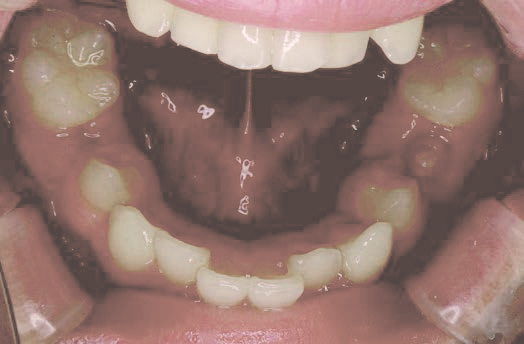

でこぼこ

でこぼこでも大丈夫。抜かずに、あごから育てる矯正治療

Jさん (矯正開始時:8歳)

Before

After

歯がガタガタに並んでいて、前歯の真ん中の位置が少し左にずれていました。

奥歯が生えるためのスペースが足りず、永久歯が生えて来られない状況が確認できました。

また、飲み込むとき下くちびるに力が入ってしまうクセが見られ、お顔全体の成長が遅れている様子が確認できました。

治療を終えて

歯がきれいに生えるためのスペースをしっかり確保することができ、歯並びを乱していたお口のクセも改善されたため、奥歯が生えるスペースを確保することができました。

しっかり噛めるかみ合わせを作ることが、将来の健康につながるので「よく噛む」練習も続けてもらっています。

主訴・治療内容 歯がガタガタになってきたことに悩み、無料相談に来院されました。

治療期間 3年

費用 462,000円(税込)